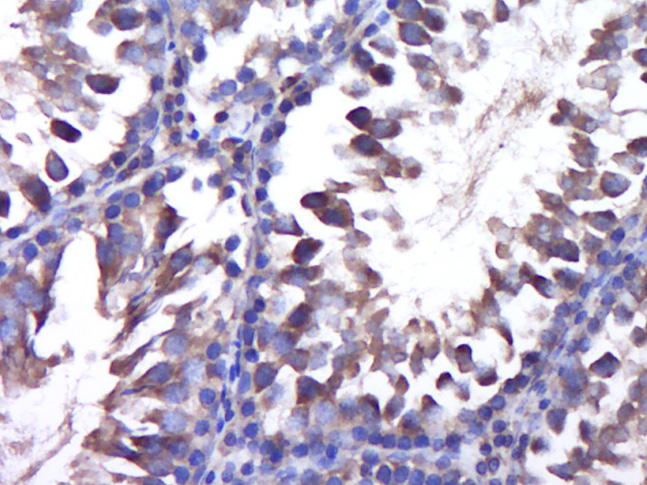

Paraformaldehyde-fixed, paraffin embedded (Rat testis); Antigen retrieval by boiling in sodium citrate buffer (pH6.0) for 15min; Block endogenous peroxidase by 3% hydrogen peroxide for 20 minutes; Blocking buffer (normal goat serum) at 37°C for 30min; Antibody incubation with (PPP3CC) Polyclonal Antibody, Unconjugated (bs-19973R) at 1:400 overnight at 4°C, followed by operating according to SP Kit(Rabbit) (sp-0023) instructions and DAB staining.